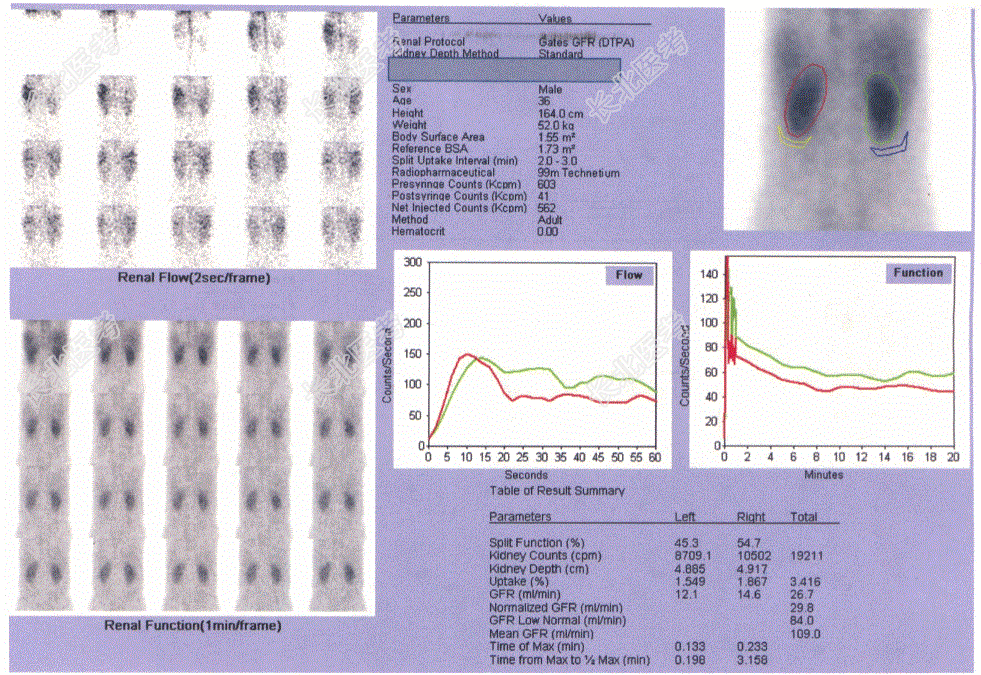

- [材料题] 患者,男,36岁,腹胀伴全身水肿1周,门诊血肌酐1038μmol/L,尿素氮20.89mmol/L。血压140~150/70~90mmHg。泌尿系彩超见双肾皮质回声增强,腹腔积液。SPECT肾显像:双肾显影放射性分布不均匀减低,肾图曲线呈低水平延长线型,双肾GFR明显减低。